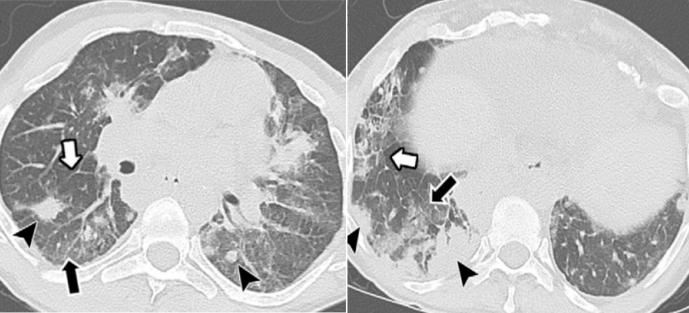

支气管扩张症是抗体免疫缺陷病患者最常见的慢性气道疾病,约47%的成年抗体免疫缺陷病患者合并支气管扩张症[21],这与促炎细胞因子表达以及黏附分子的积累有关。随着时间的推移,炎症导致气道高反应性,加重气道重塑和支气管扩张[22, 23]。在抗体免疫缺陷病患者中,免疫缺陷和失衡进一步加剧了这种恶性循环[24]。X-连锁无丙种球蛋白血症(XLA)是经典的抗体免疫缺陷病,是由Bruton酪氨酸激酶突变导致B细胞、浆细胞的数量以及血清免疫球蛋白水平显著下降[25],XLA所致支气管扩张症影像上可出现黏液嵌顿及肺部气体潴留等(图2)

图片

图2  左:XLA患者肺部CT显示右下叶支气管扩张、马赛克征左下叶肺不张伴支气管扩张(白框箭头)[26];右:34岁XLA男性患者,肺部CT显示左下叶支气管扩张,大量的黏液阻塞(白实箭头)并导致左下叶肺气体滞留[26]

图片来源:Imaging Features of Primary Immunodeficiency Disorders (DOI: 10.1148/ ryct. 2021200418)